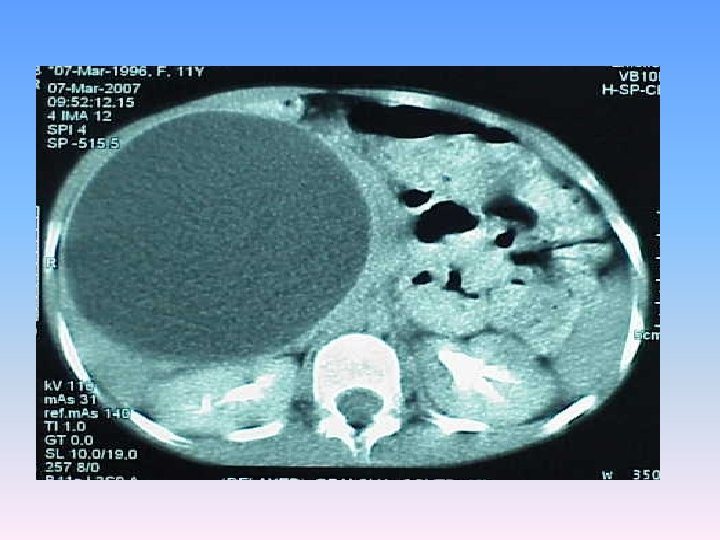

Abdominal CT Scan § A regular lobulated cystic mass in right lobe of liver (120 x 120) without calcification causing dilatation of intra & extra biliary ducts.